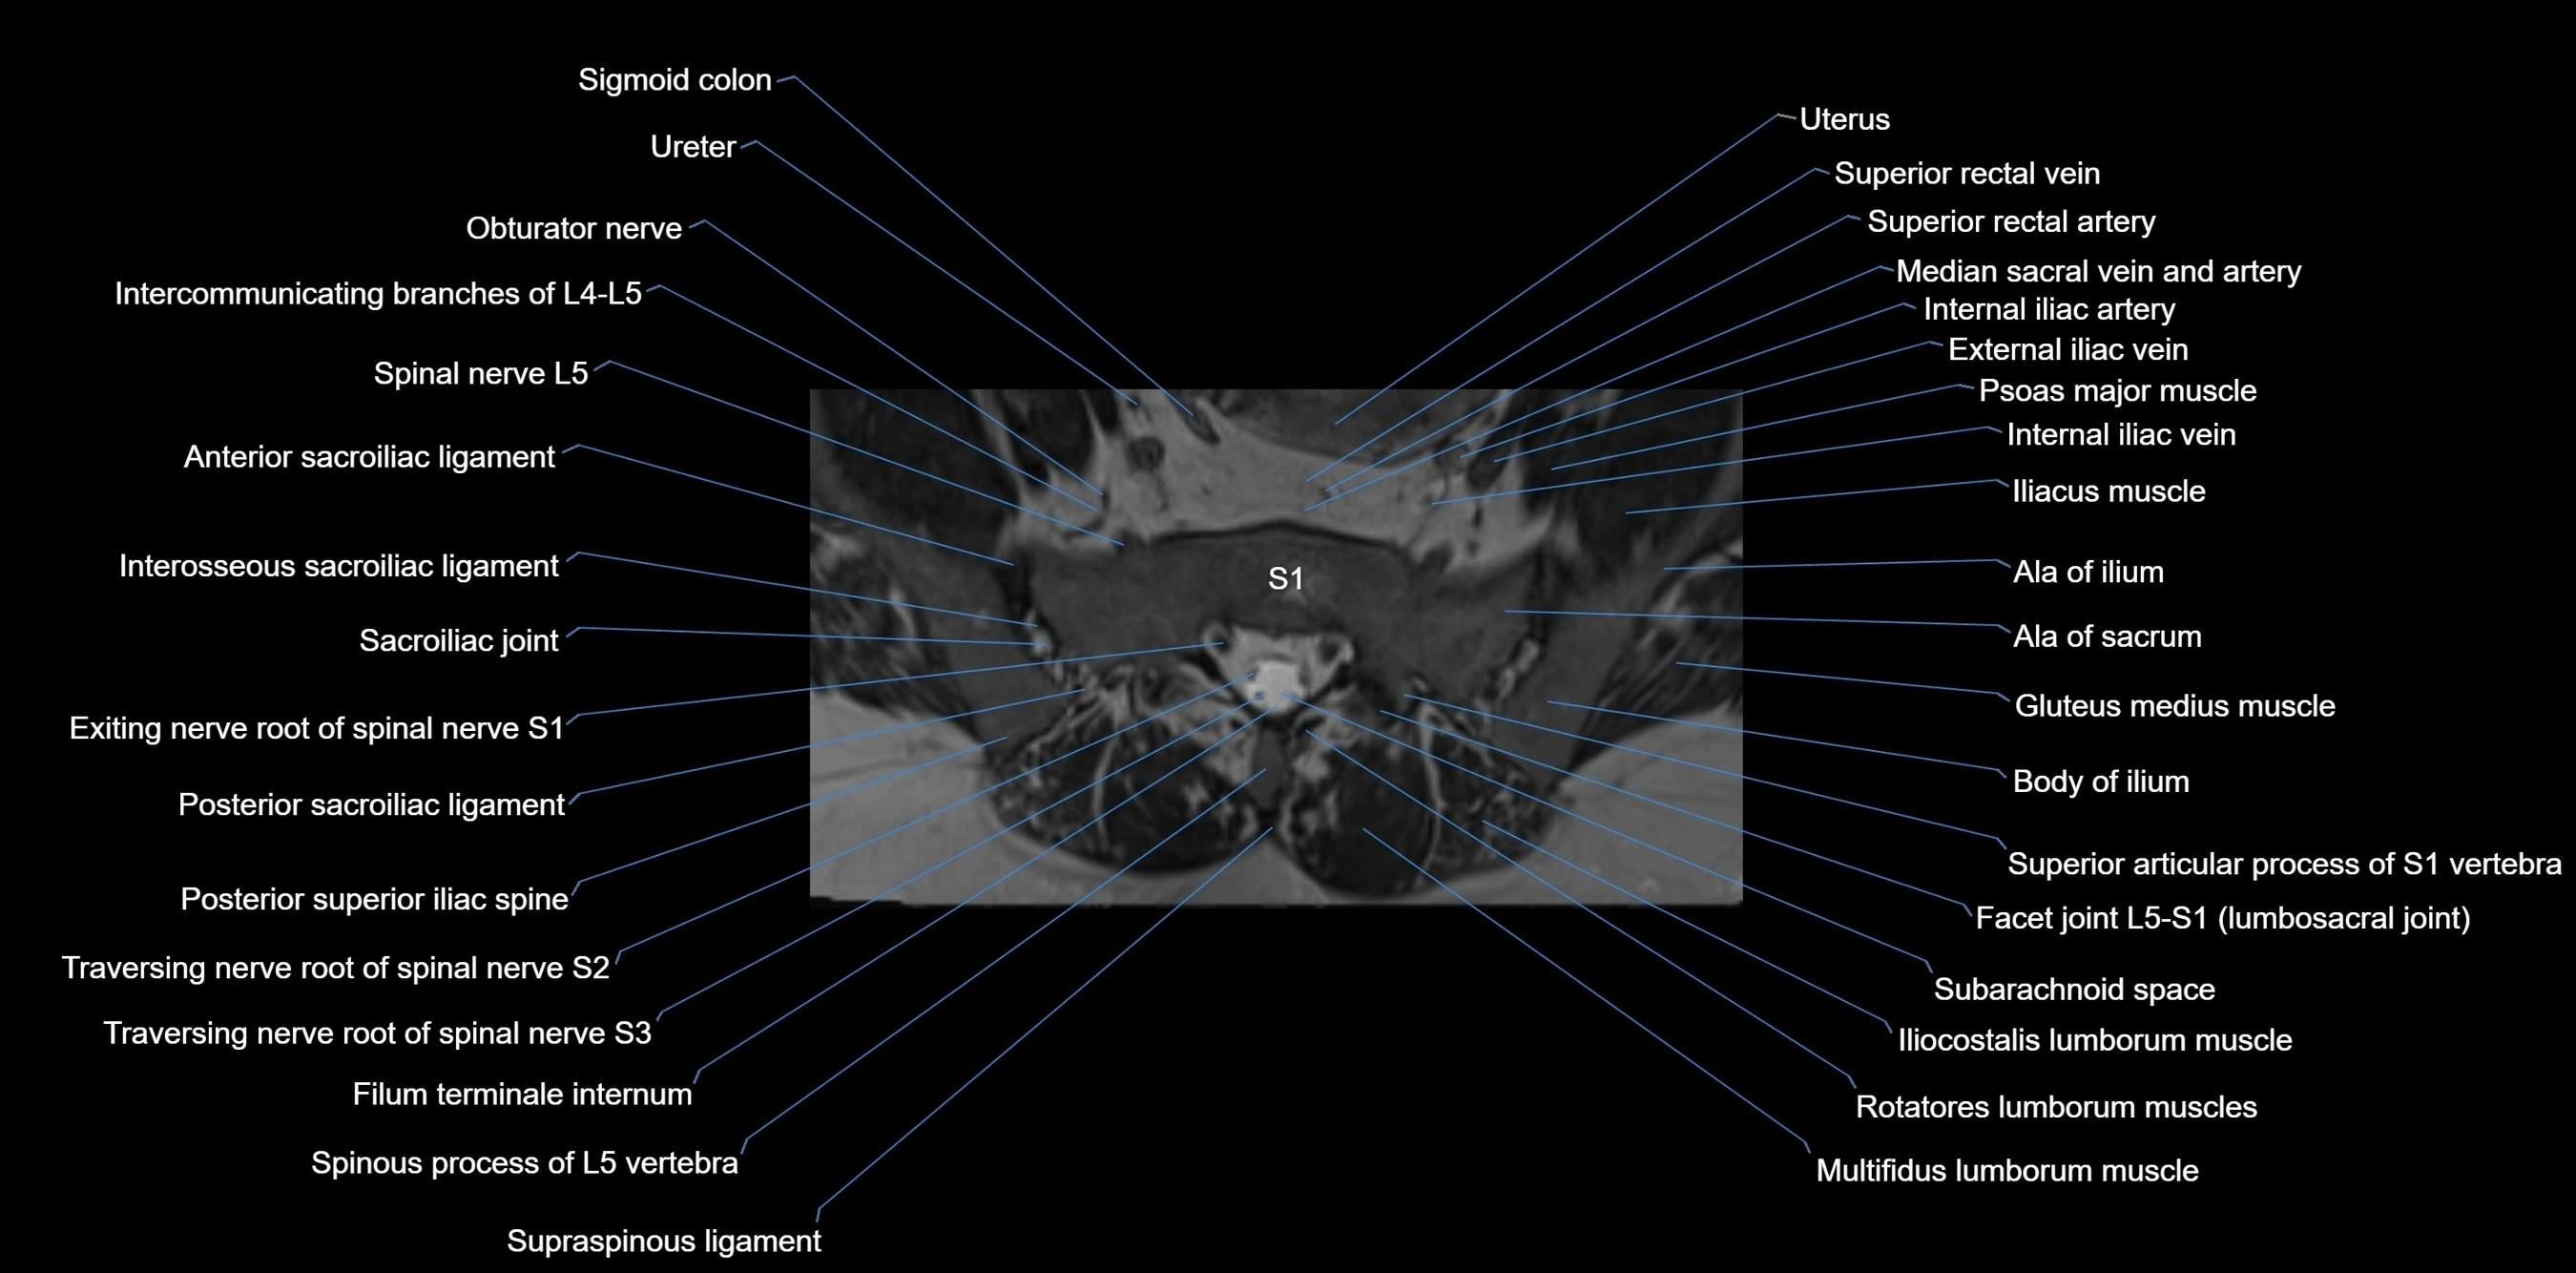

MRI image

image